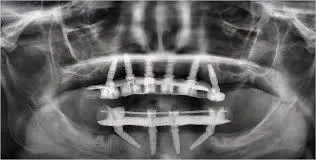

“All-on-4” refers to a full arch of teeth supported by four dental implants. “All-on-X” is a broader term that allows for additional implants—usually five or six—depending on your bone quality, anatomy, and clinical needs.

The All-on-4 technique strategically places implants at angles to maximize existing bone. However, in certain cases—especially with significant bone loss—some grafting may still be recommended in order to improve long term success.